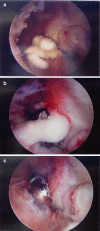

Elbow motion is essential for upper extremity function to position the hand in space. Unfortunately, the elbow joint is prone to stiffness following a multitude of traumatic and atraumatic etiologies. Elbow stiffness can be diagnosed with a complete history and physical exam, supplemented with appropriate imaging studies. The stiff elbow is challenging to treat, and thus, its prevention is of paramount importance. When this approach fails, non-operative followed by operative treatment modalities should be pursued. Upon initial presentation in those who have minimal contractures of 6-month duration or less, static and dynamic splinting, serial casting, continuous passive motion, occupational/physical therapy, and manipulation are non-operative treatment modalities that may be attempted. A stiff elbow that is refractory to non-operative management can be treated surgically, either arthroscopically or open, to eliminate soft tissue or bony blocks to motion. In the future, efforts to prevent and treat elbow stiffness may target the basic science mechanisms involved. Our purpose was to review the etiologies, classification, evaluation, prevention, operative, and non-operative treatment of the stiff elbow.